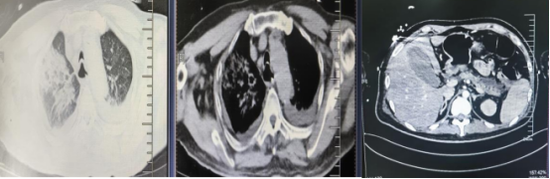

年仅25岁,既往有痛风、糖尿病却未规律治疗的他,入院时已面临双肺严重感染、腹腔积液、呼吸窘迫,多器官功能衰竭风险极高的局面,被直接送入重症医学科(ICU)抢救。

第一时间为患者建立生命支持:紧急实施气管插管呼吸机辅助呼吸,纠正严重低氧血症;同时启动连续性肾脏替代治疗(CRRT),稳定其紊乱的内环境,清除体内过载的炎症介质。针对凶险的感染,团队精准控症,使用强效抗生素对抗包括肺炎克雷伯杆菌、鲍曼不动杆菌在内的多重耐药菌感染。通过精准抑制胰腺分泌、积极补液消酮、严格控制血糖等一系列组合拳,为患者赢取宝贵的治疗时机。

此外,团队还及时进行外科干预,在超声引导下对患者肝肾间隙、脾肾间隙的脓肿进行了穿刺置管引流,有效控制了感染源头。

经过17个日夜的全力救治,薛先生的生命体征逐渐平稳,神志转清,成功脱离了呼吸机支持,血氧饱和度稳定在98%以上。后续复查显示,其胰腺周围渗出明显吸收,肺部感染情况大幅好转,腹腔积液显著减少。